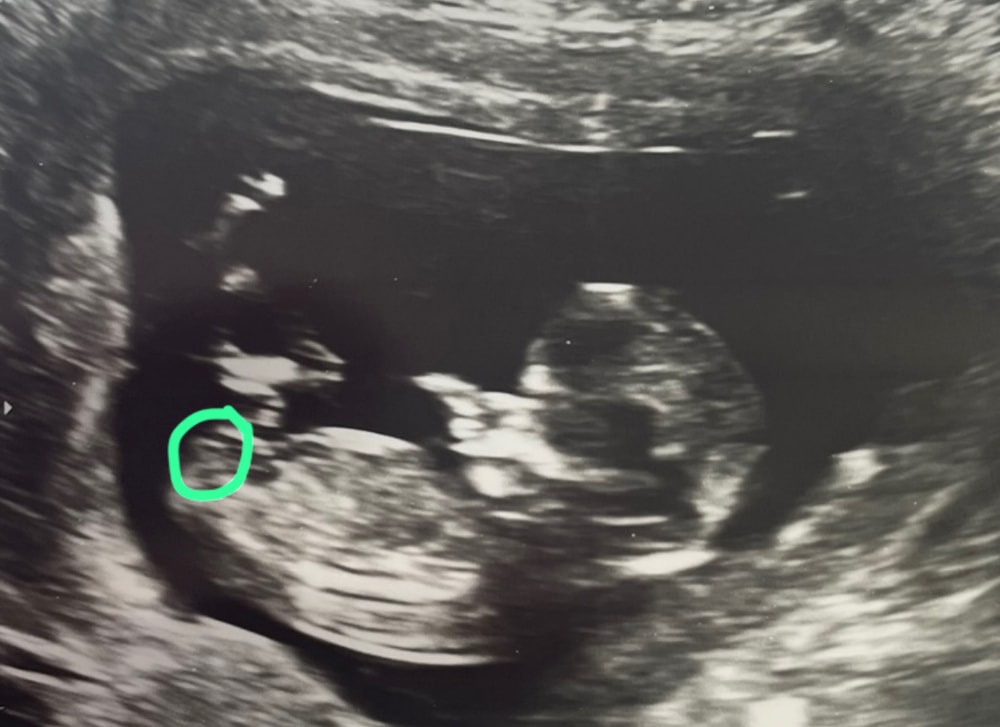

Половой бугорок

Пока не понятно

Не видно бугорка.

Может это бугорок и девочкаИзображение

Марина, ну вот смотрите на эту фотку и думайте, что это девчачий бугорок.. 😅больше как-то здесь ничего другого не видно